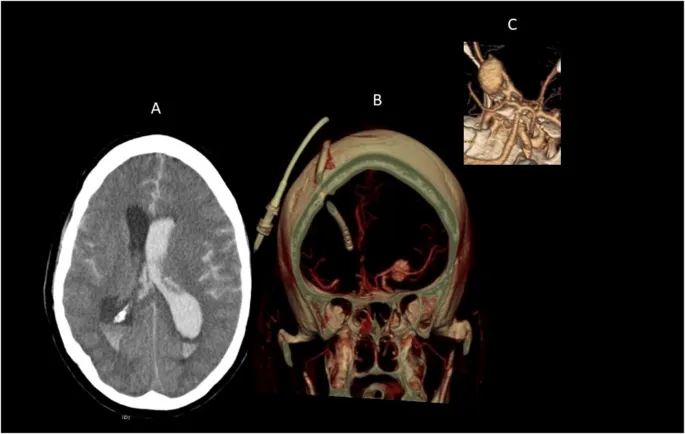

- Subarachnoid Hemorrhage (SAH): Thunderclap headache, neck stiffness.

⭐ The 'worst headache of life' or 'thunderclap headache' is a classic presentation of subarachnoid hemorrhage and requires urgent neuroimaging.

- Subarachnoid hemorrhage (SAH): "Worst headache of life"; CT scan is key.